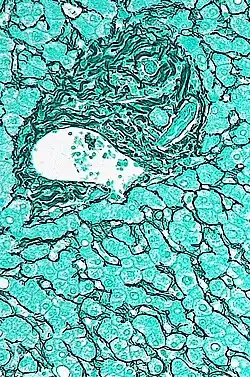

Espacio porta en el que puede verse un conductillo biliar, arteria y vena. | ||

En histología del hígado, los espacios porta son estructuras tubulares tridimensionales, de tejido conjuntivo fibroso, situados en la periferia de los lobulillos hepáticos. Se originan en el hilio del hígado y se distribuyen en el interior de este órgano, siguiendo un patrón de ramificación sucesivo. Cada uno de los espacios porta contiene una tríada porta, integrada por: una arteriola rama de la arteria hepática, una rama de la vena porta hepática, un conductillo biliar.[1][2]

Si consideramos el lobulillo hepático tridimensional, que posee forma de prisma hexagonal, como la unidad funcional del hígado, los espacios porta se ubican en las seis aristas de la periferia.[3]

En su espesor llevan las ramificaciones de: la arteria hepática, de la vena porta, del conducto biliar, de vasos linfáticos y de fibras nerviosas.[1]